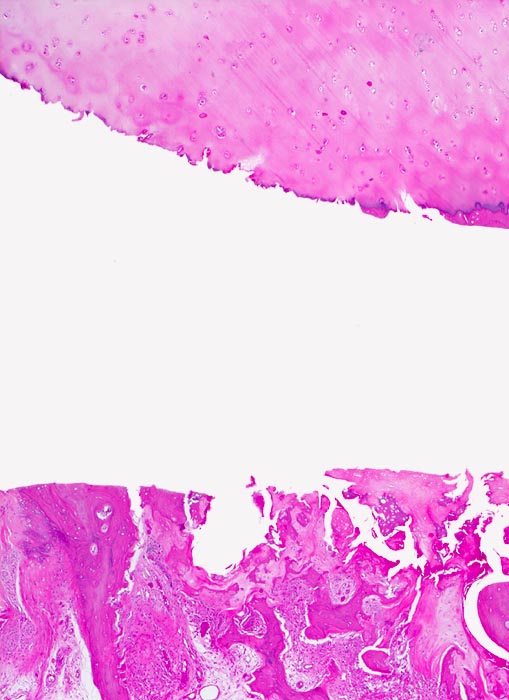

Makroskopisch ist die Nekrose im Anfangsstadium durch eine intensiv gelbe Verfärbung mit hämorrhagischem Randsaum charakterisiert. Häufig kommt es zur flächenhaften Ablösung des ansonsten intakten Gelenkknorpels (DD Arthrose!) zwischen subchondraler Knochenlamelle und angrenzender Spongiosa. In den Spätstadien sind die Nekrosezonen grau-gelb gefärbt und von körniger Konsistenz. Ein Teil der nekrotischen Spongiosabälkchen dient als Leitschiene für die Neubildung von Osteoid und mineralisierten Trabekeln, die an der Aussenseite angelagert werden. In der Nekrosezone kommt es zur Sequestrierung von Knochenbälkchen durch Frakturen. Die Markräume werden bindegewebig organisiert. In der Peripherie besteht initial ein hyperämischer Randsaum und im Verlauf kommt es zur Ausbildung einer metaplastischen Knorpel- und Knochenneubildung mit Randsklerose. Das Endstadium der Abräumreaktion untergegangener Knochenabschnitte stellt eine meist subchondral lokalisierte pseudozystische Umwandlung dar. Schliesslich kollabiert der Femurkopf und der Verlust der Gelenkkongruenz führt zu einer fortschreitenden sekundären Coxarthrose (> 3192)

• Flächenhafte Ablösung des gut erhaltenen Gelenkknorpels zwischen subchondraler Knochenlamelle und angrenzender nekrotischer Spongiosa.

• In der Nekrosezone osteoklastäre Resorption von avitalen sequestrierten Spongiosabälkchen.

• Ortsständiger Lamellenknochen wird als Leitschiene zur Fasernknochenneubildung benutzt.

• Pseudozystische Hohlräume in den nekrotischen Markräumen.

• Fibrosiertes Mark mit einzelnen thrombosierten Arterien.